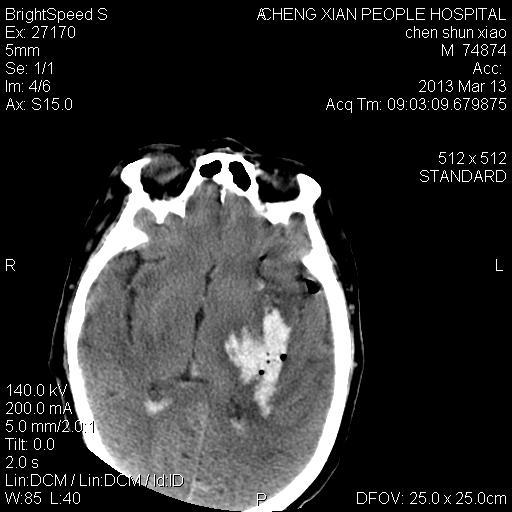

患者陈++,男,71岁。因“昏迷四小时,伴右侧肢体活动受限”以“脑出血”收住院。发病后12小时用“改良立体定向-软通道微创介入新技术治疗脑出血”。术后24小时颅内出血大部被清除,患者神志清晰。右侧肢体肌力0级。

患者陈++,男,71岁。因“昏迷四小时,伴右侧肢体活动受限”以“脑出血”收住院。发病后12小时用“改良立体定向-软通道微创介入新技术治疗脑出血”。术后24小时颅内出血大部被清除,患者神志清晰。右侧肢体肌力0级。